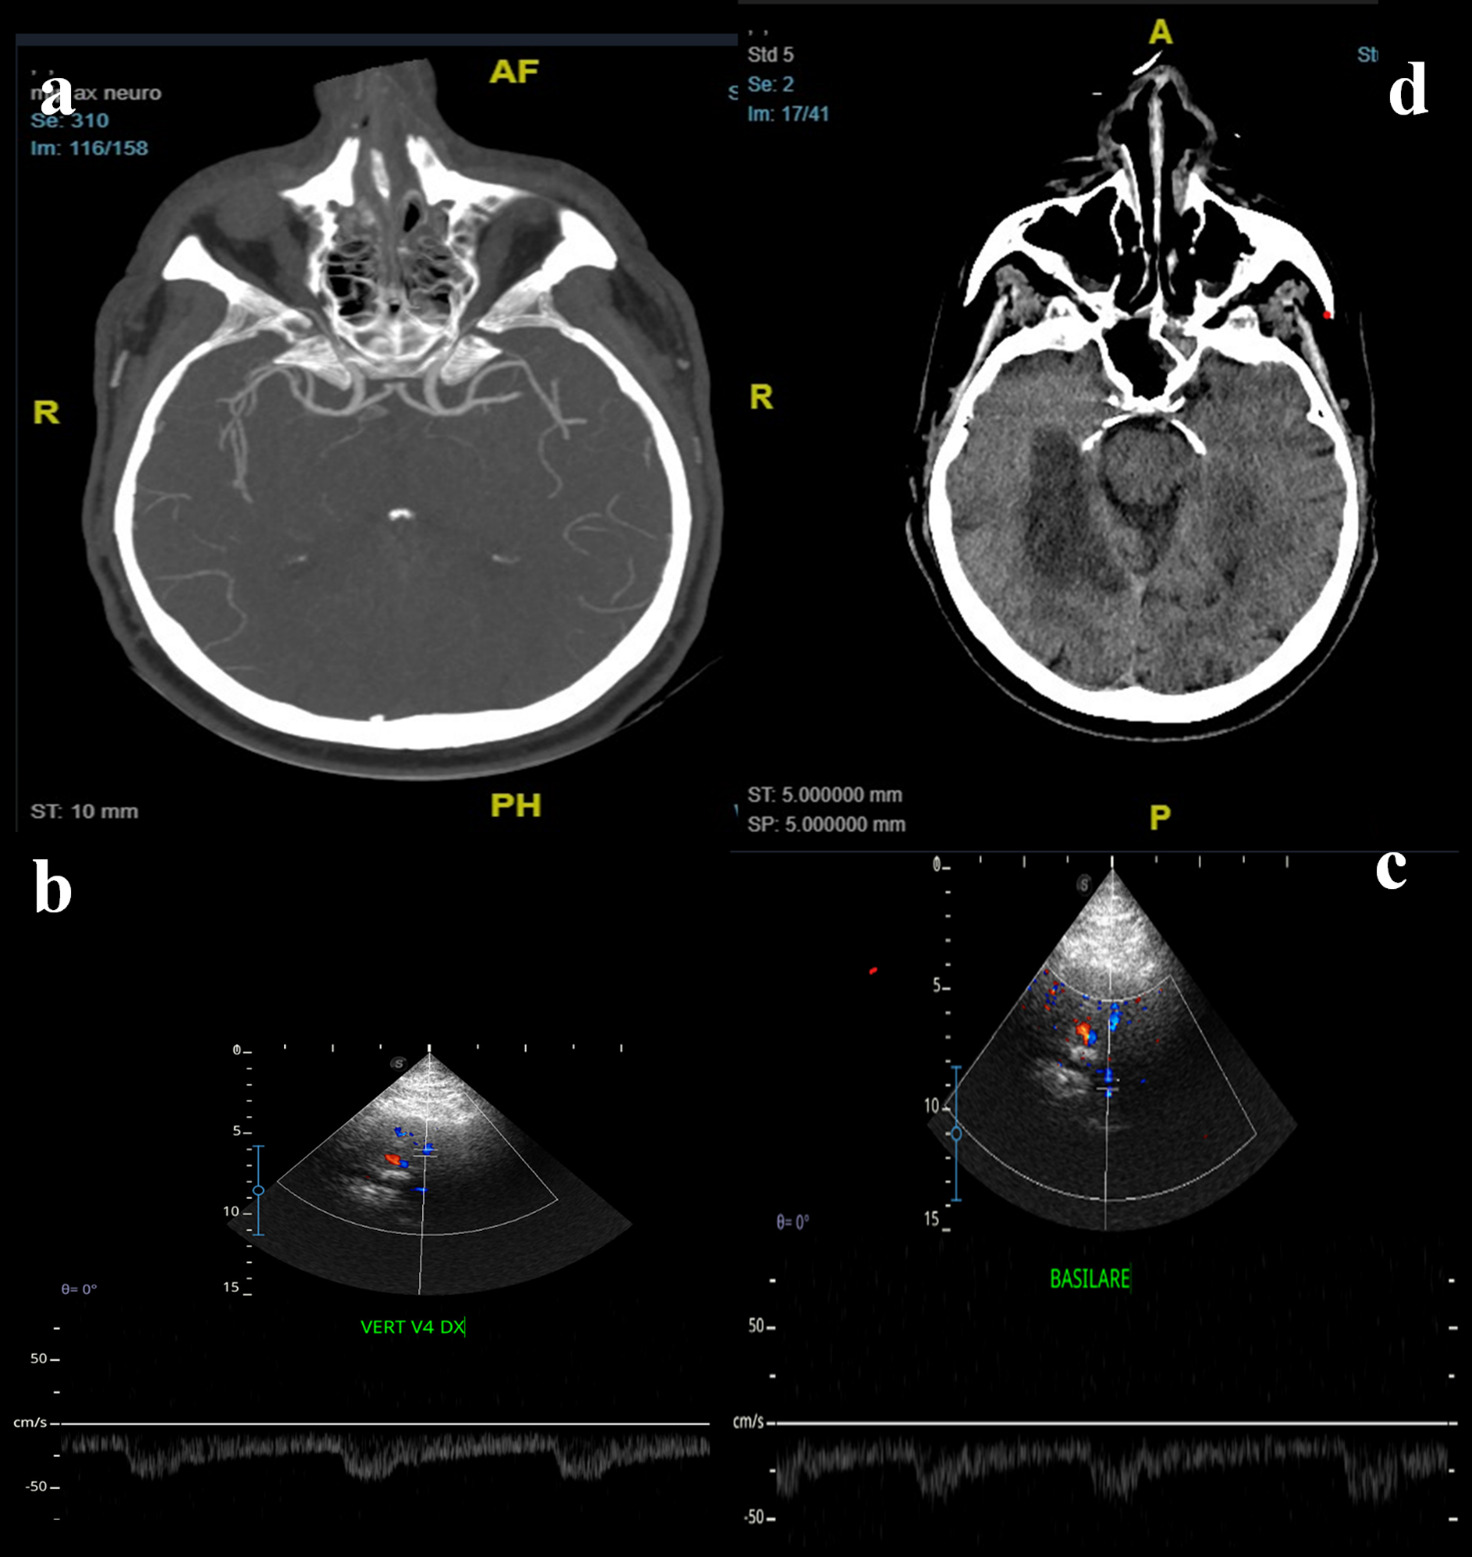

Figure 5. A 65-years-old man came to the hospital for acute loss of consciousness. His medical history revealed paroxysmal atrial fibrillation, hypertension, smoking, dyslipidemia, and COPD. In ER department he underwent CTA that showed thrombotic occlusion of the top of basilar artery (a), with normal flow of the vertebral-basilar axis near the occlusion. The patient also had an aortic dissection, so thrombolysis was contraindicated. The patient was treated by mechanical thrombectomy: DSA showed occlusion of the distal third of the basilar artery and of P3-segment of right cerebral posterior artery. After the successful procedure, TCCS was employed to monitor the posterior hemodynamic pattern. TCCS detected normal flow at the origin of the basilar (b) and at the vertebral arteries (c). The patient was admitted to the Intensive Care department, and the 24-hour control brain CT showed a right cerebellar infarct and bilateral thalamic infarcts (d). Neurological examination showed right facio-brachio-crural hemiparesis. Anticoagulant therapy was administrated. The patient showed an important improvement of his conditions and at the time of discharge, associated with regular flow in basilar artery.

Figure 6. A 57-years-old man was admitted to the ER department for acute dysarthria, dysphagia, and dysmetria; the neurological examination showed left facio-brachio-crural hemiparesis, ocular ptosis (left eye), left facial hypoesthesia, dysmetria and dysarthria. He underwent CTA that showed left vertebral artery occlusion and left cerebellar and brainsteam infarction. The patient was treated by thrombolysis and mechanical thrombectomy: DSA showed occlusion of the vertebro-basilar junction and of P1-segment of right cerebral posterior artery (a), so a stent was placed at the vertebro-basilar junction. Control brain CT (b) showed multiple infarcts in bilateral cerebellar territory and right temporo-occipital hemisphere. TCCS (c) showed normal hemodynamics at right ACP, so medical treatment was continued. A TCCS (d,e) performed after one week showed normal flow velocity in the basilar and vertebral arteries. At discharge, neurological examination showed improvement in symptomatology.